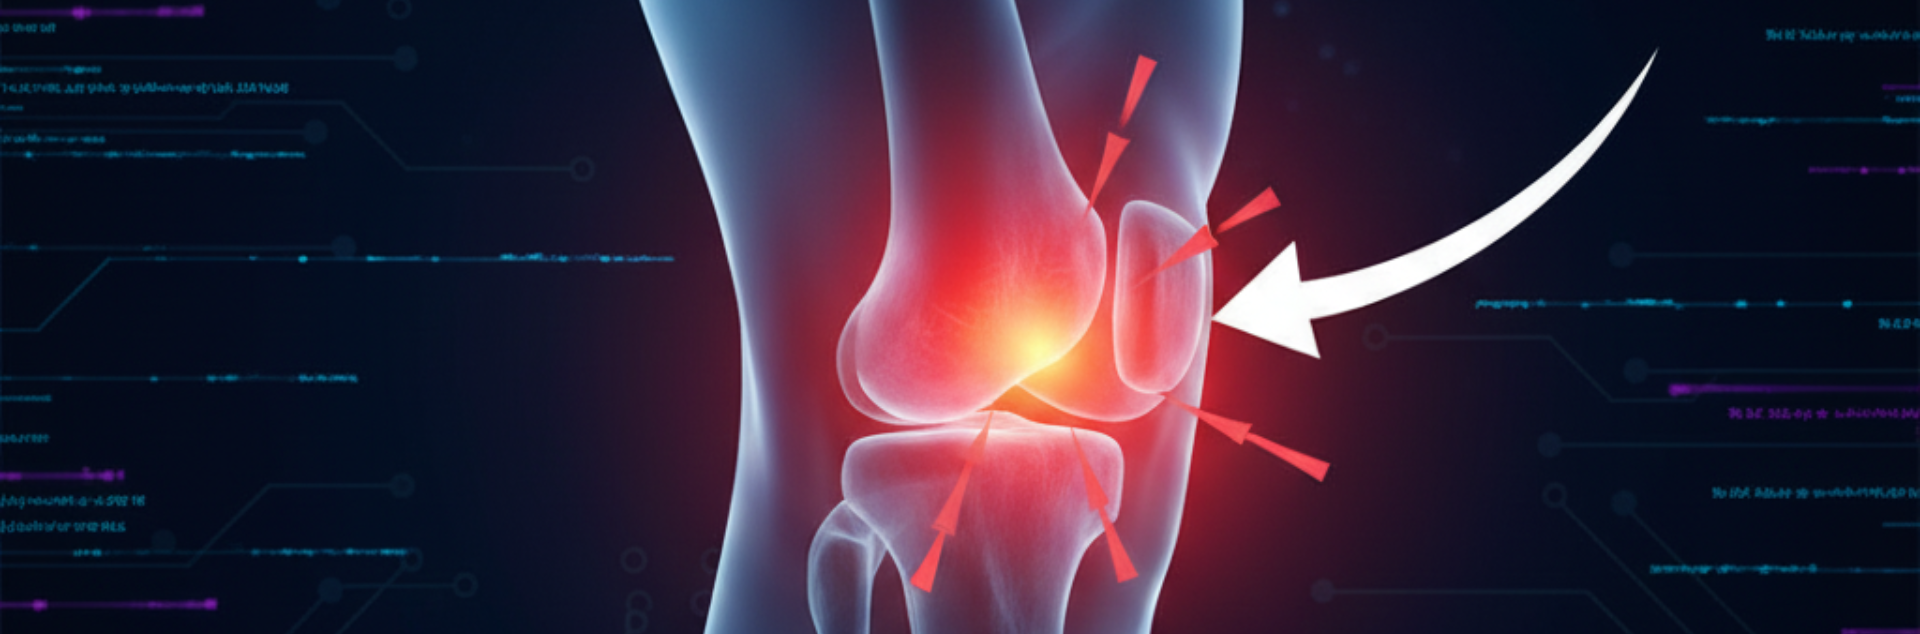

Runner Knee

Runner’s Knee, also known as Patellofemoral Pain Syndrome, is a common condition that causes pain around or behind the kneecap. Despite its name, it doesn’t only affect runners; anyone engaging in repetitive knee-bending activities or daily movements can experience this condition.

- Pain Location:Typically felt in the front, sides, or all around the knee.

- Swelling:Mild swelling around the kneecap is common in more severe cases.

- Maltracking of the Patella

When the kneecap moves improperly within its groove, it can irritate the cartilage and surrounding tissues, causing pain and inflammation.